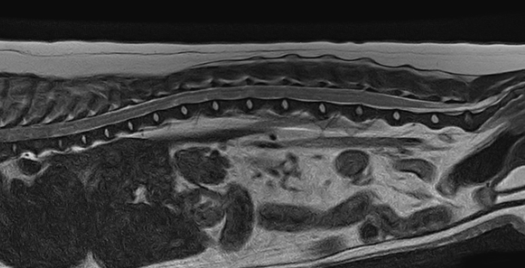

정상 디스크

급성 추간판 탈출증 환자

02척추 MRI

· 통증, 마비의 원인 진단

· 척추 실질 질환의 진단

· 추간판 탈출증, 척수공동증, 척수연화증 등